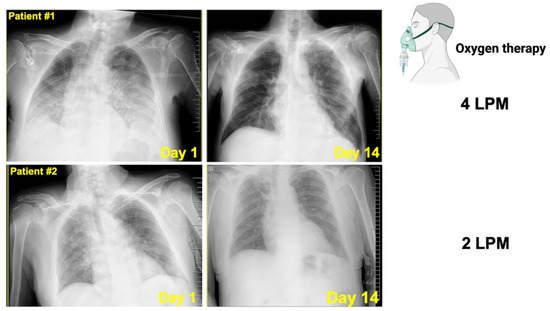

2.1. Outcomes of Two Hospitalized Patients with Active Cancer and COVID-19 Orally Receiving the Silibinin-Containing Nutraceutical Legalon®

2.1.1. Patient #1

2.1.2. Patient #2